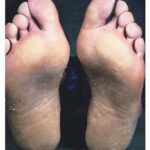

EPPK also known as Vörner’s disease, first described in 1901 and diffuse NEPPK also called Unna-Thost type, after the clinicians who first reported it, are often phenotypically confused (1-3). Both are present from infancy and are characterized by hyperkeratosis covering the entire palms and soles. EPPK tends to have thick fissured pattern, which is bordered with erythematous margins; compared with NEPPK (Figure 2a) which usually has a more yellow waxy appearance though the phenotype in both diseases can vary greatly even within a family. The lesions on the skin in NEPPK are often susceptible to secondary dermophyte infection and hyperhidrosis is common. Spreading onto the dorsal surfaces of the hands and wrists with a sharp cut off is a feature of NEPPK, though knuckles pads can be present in EPPK. Nail changes may be observed in both disorders. Both diseases are inherited in an autosomal dominant fashion and are highly penetrant.

Erythrokeratodermia variabilis (EKV) is a phenotypically variable disease and was first described in 1925 (22). It is an autosomal dominant disease, which presents either at birth or within the first year as diffuse thickening of the palmoplantar epidermis with persistent generalized pigmented rough hyperkeratosis (fig. 2c). Patients also suffer from symmetrically distributed fixed hyperkeratotic plaques, which are sharply demarcated and can persist for months or years. Transient erythematous areas occur independently to the hyperkeratosis, lasting from minutes to days, and are usually preceded by a burning sensation (fig. 2d). Both the hyperkeratosis and erythematous patches can be triggered by trauma to the skin, temperature changes, UV exposure, and emotional stress. The lesions affect the whole body but are more often found on the face, buttocks and extensor surfaces of the limbs. Histologically EKV shows no specific features, but there is generalized hyperkeratosis, acanthosis, papillomatosis, dilated capillaries and perivascular infiltration. With increasing age the areas of the body affected by EKV become more restricted to the palmoplantar epidermis.

Meleda disease (Mal de Meleda) shows transgressive palmoplantar keratoderma that occurs shortly after birth. This starts with redness on the palms and soles shortly followed by scaling and thickening which then spreads to the dorsal surfaces of the hands and feet and to other body parts, the knees and elbows and other sites of traumatic stress are particularly affected. Hyperhidrosis and perioral erythema are other features associated with Mal de Meleda. This PPK is autosomal recessive and has been identified in a number of consanguineous families, in which linkage analysis has placed the gene at 8qter (31).

Vohwinkel’s syndrome also known as keratoderma hereditaria mutilans, first described in 1929 (32) is a rare autosomal dominant disorder, which manifests as hyperkeratosis of the palms and soles with a honeycomb appearance. Patients also suffer from constrictions of the skin around the digits (pseudo-ainhum), which can lead to autoamputation due to impairment of circulation and deformity of the underlying bone (Figure 2b). Also seen in these patients are starfish shaped hyperkeratotic lesions on the dorsal surface of the hands. The histopathological definition of Vohwinkel’s syndrome is a thickened stratum corneum, hypergranulosis and particularly hyperkeratosis with round nuclei retained in the stratum corneum. There is overlap of the clinical features of Vohwinkel’s syndrome and other disorders, for example, pseudo-ainhum have been seen in both discoid lupus erythematosus and Mal de Meleda (33, 34).